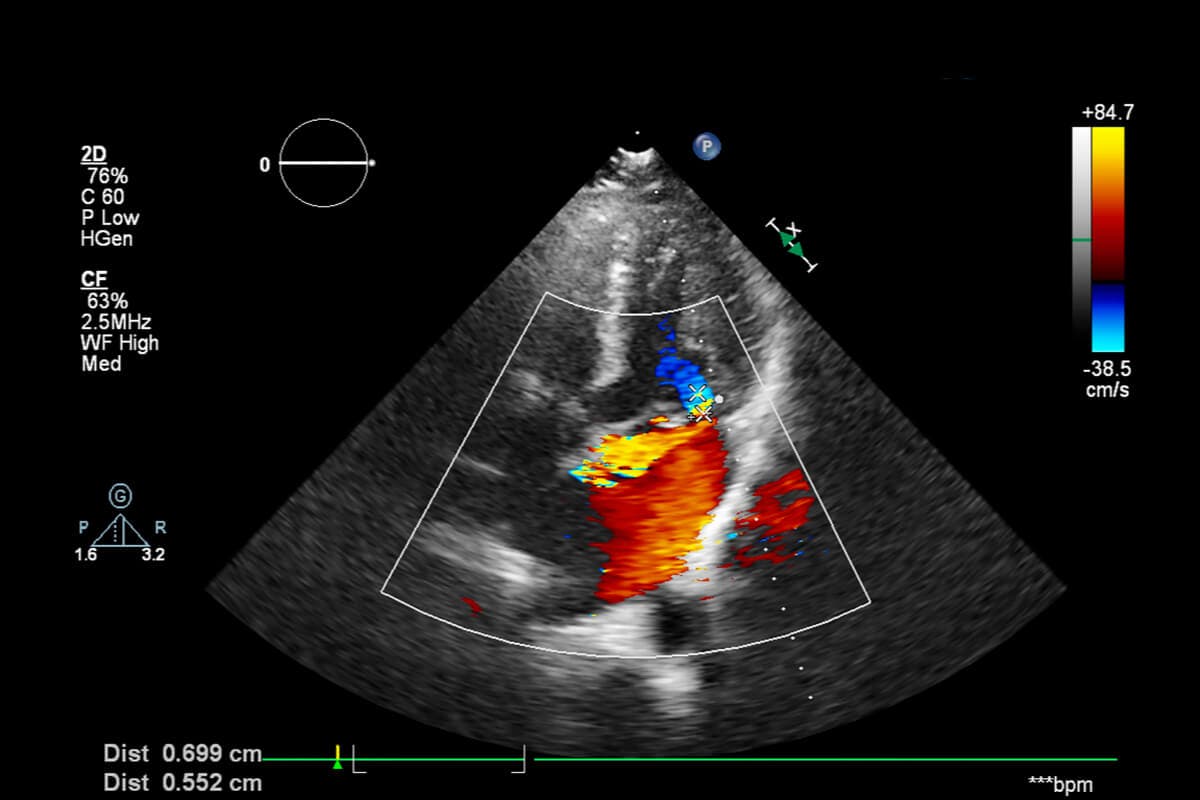

Flere oppfølgende Doppletester anbefales. De utføres nesten alltid hver 15. dag for å overvåke utviklingen. I tillegg skriver legen ut type 3 kompresjonsstrømper.